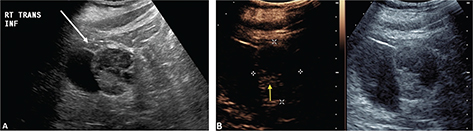

CEUS can be used to follow patients for residual or recurrent tumor with high accuracy. Any residual tumor will be identified as areas of increased enhancement. Absence of blood flow as in Figure 3B confirms complete ablation of the renal tumor. Note that it is not possible to determine if contrast is not utilized in Figure 3A. Figure 4 demonstrates a case where residual tumor (calipers) is present.

Figure 3. Successful ablation. Patient presented for 3-month post-RFA evaluation. (A) B-mode image before the ablation. Large heterogeneous tumor is noted on gray scale examination (arrow). (B) Absence of residual blood flow (arrow) is demonstrated on CEUS examination.

Fig 4

Figure 4. Tumor recurrence/inadequate ablation. Patient presented for CEUS examination 6 weeks after RFA. (A) The B-mode image demonstrates a complex mass (arrow) with solid and cystic components. It is not possible to determine if there is residual tumor. (B) CEUS image demonstrates the tumor (calipers) with residual flow in the posterior part of the tumor (arrow).